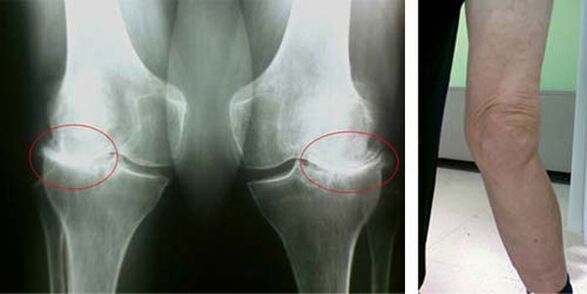

Les étapes initiales de l'apparition d'une pathologie telle que l'arthrose de l'articulation du genou ne se manifestent en aucune façon visuellement. Cependant, après un certain temps, le patient remarque des signes de déformation du genou, ainsi qu'une courbure caractéristique le long de l'axe du bas de la jambe (dirigée vers l'intérieur). Il y a aussi un craquement lorsque vous devez plier la jambe.

La présence de douleur, un mouvement limité du genou oblige une personne à consulter un médecin et à subir un examen. Pour ce faire, il doit passer des tests et passer une radiographie de l'articulation malade. Si ces mesures ne suffisent pas à confirmer l'arthrose de l'articulation du genou, une imagerie par résonance magnétique est réalisée. Sur la base des données collectées, le médecin choisit les meilleures méthodes de traitement.